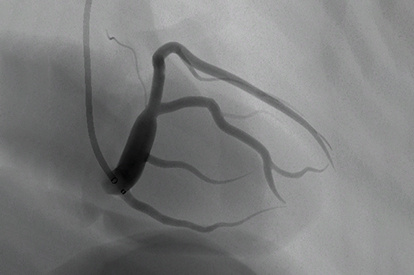

Coronary Intervention Module

Transradial Coronary Intervention Module

Coronary Bifurcation Module

Coronary CTO Module